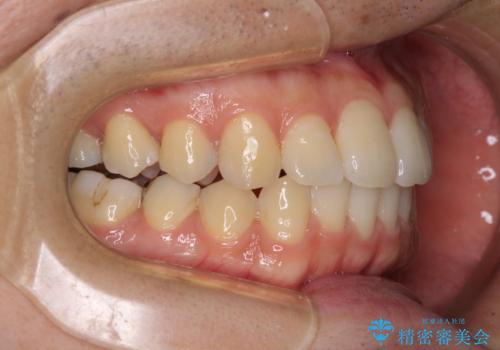

インビザライン・ライトによる矯正治療の後戻り改善

- 矯正治療の後戻りを気にして来院された患者様です。

後戻りは軽微でしたので、インビザライン・ライトにより矯正治療を行うこととしました。

再矯正後の後戻りを防ぐため、歯列排列後に、下顎前歯はワイヤーによる固定を行いました。

下顎前歯の歯列を動かないようにしておくことで、上顎前歯の後戻り防止にも効果を発揮します。